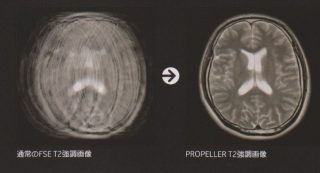

- 前回、「検査中はじっと寝ていましょう」と書きましたが、動いたらどうなるかというと、ひどい場合には、下の左側の画像になってしまいます。(ちなみに右側のような画像になって欲しい!)

これでは、病気の診断が難しいですね。ある程度動いても撮影できるものありますが、当院の装置では、まだまだ全部のものに対応できていません。これも装置の力に因ります。残念。